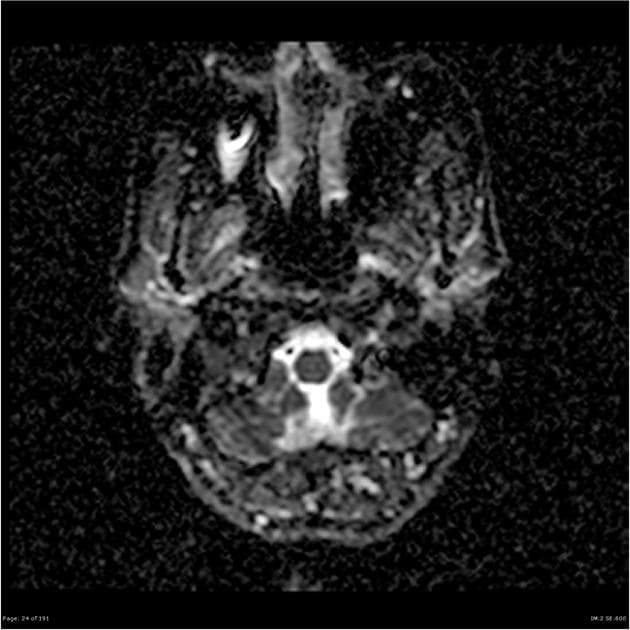

Axial ADC

- Không thấy hạn chế khuếch tán (restricted diffusion).

- "Hiện tượng bắt thuốc dạng viền không hoàn chỉnh, không hạn chế khuếch tán và không có hiện tượng nở bóng trên T2* giúp phân biệt với áp xe hoặc u."